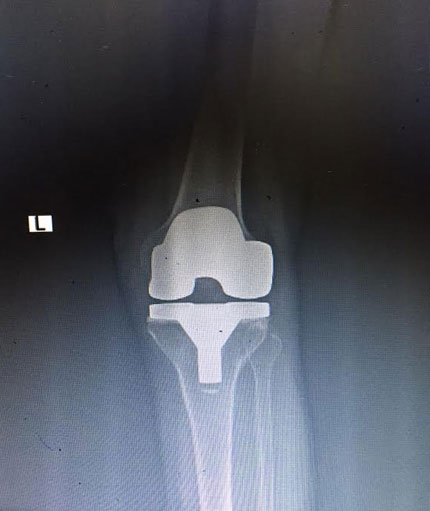

Knee Replacement

Knee replacement surgery otherwise knee arthroplasty, is a surgery involving the replacement of the damaged, diseased or distorted joint surfaces of the knee, with a prosthesis. As per the condition of the patient’s knees, the surgery can be performed as a partial knee replacement surgery or the total knee replacement surgery.